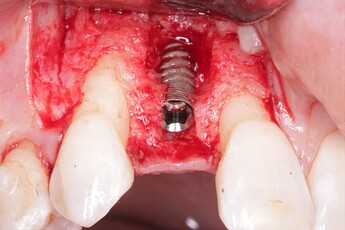

An implant was placed in site #7 with an existing buccal bone defect (Pictures 1 & 2). Prior to placing the bone graft over the implant, the membrane is measured and trimmed and tucked under the palatal flap trying to avoid wetting the entire membrane (Picture 3). The particulate bone graft (DALI Classic Cortical Cancellous Mix) is placed over the implant surface to restore the defect (Picture 4). The membrane is folded over the crest and onto and slightly beyond the particulate bone graft while slowly dropping saline onto the membrane (Picture 5). This enables the membrane to contour and drape over the graft and “seal” the graft off from the surrounding soft tissue (Picture 6 and 7). Sutures are then used to achieve primary closure over the GBR site (Picture 8).

Pic 1

osseoseal-1